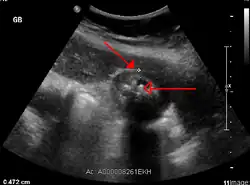

Ultrasonografia (USG) może wykazać obecność kamieni, pogrubienie ścian pęcherzyka żółciowego i okołopęcherzykowy płyn. Tomografia komputerowa (TK) może być przydatna w wykrywaniu powikłań[6].

Przewlekłe zapalenie pęcherzyka żółciowego jest rozpoznawane na podstawie typowego obrazu w USG, gdzie stwierdza się grubościenny, zniekształcony pęcherzyk żółciowy z obecnością złogów[8].